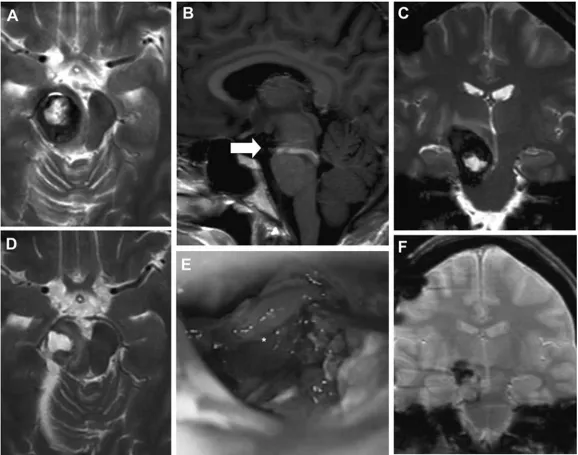

祸兮福所倚,福兮祸所伏。一路磕磕绊绊,本以为可以一直幸福下去的陈女士,再次出现体征。分娩两个月后,陈女士出现左侧面部麻痹,经MRI证实脑桥切除腔再出血。与最初的图像相比,在脑桥区发现一个脑干海绵状血管瘤残余或复发,更多的是背侧和下方(图2)。T1核磁共振造影(考虑到胎儿安全,未在妊娠期间进行)显示竟是一个巨大的发育性静脉异常(DVA,一种先天性脑血管畸形)。

图2:患者1分娩后的术前MRI(A–C)、术中视图(D)和术后MRI(E和F):轴向(A)、矢状面(B)和冠状面(C)MRI平面显示脑干海绵状血管瘤病变的残余和较大的DVA(箭头,B)。术中观察(D)显示手术腔和海绵状血管瘤少部分残留(星号)。